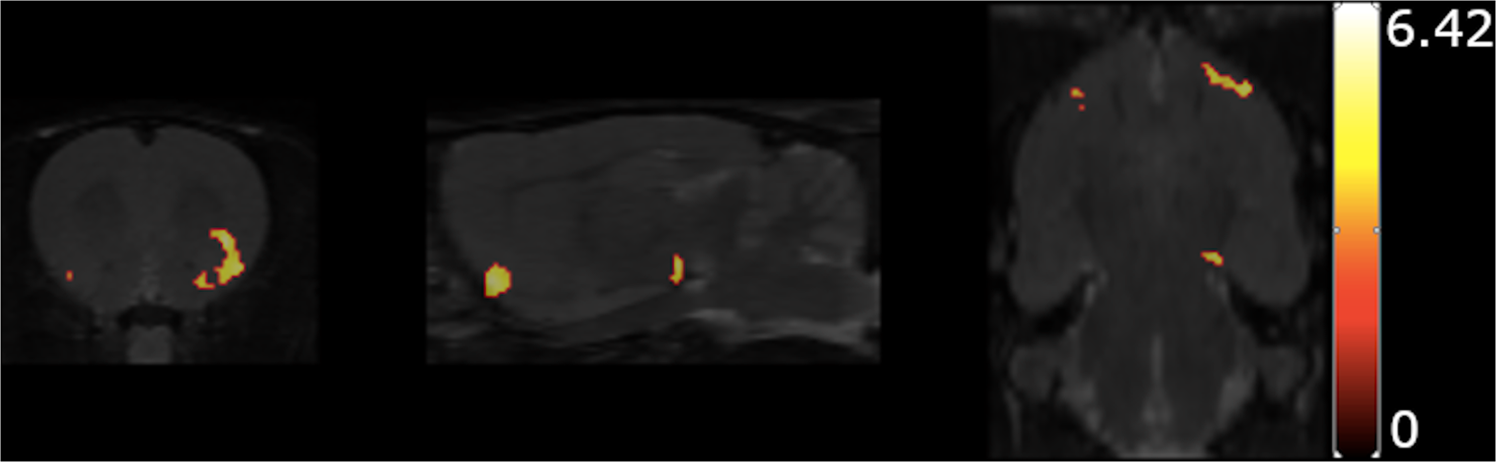

Fig. 5

Results of the voxel-wise comparison of the 5-HT2AR binding between the rats of the control group (H0/M0) and the rats treated with haloperidol at 0.25 mg/kg/day.